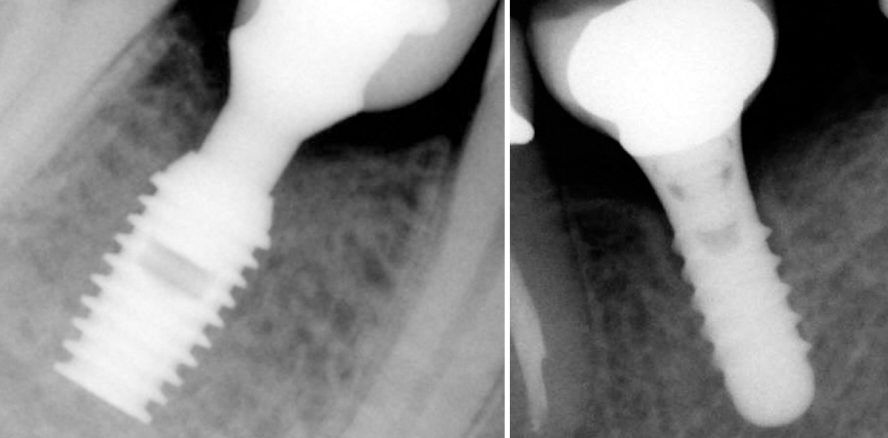

Es lässt sich hierbei erkennen, dass der horizontale Knochenanteil rund um den Halsbereichs an Kieferkammhöhe (rote Pfeile) bei den vasenförmigen Implantaten geringer ist als bei den anderen beiden Formen. Damit ist beim vasenförmigen Implantat ein geringerer Knochenanteil für die Kraftverteilung vorhanden. Somit ist es bei dieser Form wahrscheinlicher als bei den anderen beiden, dass der Knochen um dieses krestale Modul aufgrund der prothetischen Aufbissfunktion überlastet und abgebaut wird (Lemons 2004). Dieser Zustand tritt klinisch in Form von messerscharfen Rillen an den Stellen betont hervor, an denen eine geringere Menge Knochen um das krestale Modul des Implantats vorhanden ist. Die Theorie stimmt qualitativ mit den klinischen Befunden überein, bei denen vasenförmige Implantate nach einiger Zeit einen langsamen, aber fortschreitenden Knochenschwund und raketenförmige (biomechanisch günstigere) Implantate im Lauf der Zeit keinen oder nur geringen Knochenschwund aufweisen (Venuleo 2008) (Abb. 6–8). Trotz des höheren Knochenanteils um den Halsbereich des zylindrischen Kieferknochenimplantats im Vergleich zum vasenförmigen Implantat zeigen mathematische Modelle in Übereinstimmung mit den klinischen Beobachtungen, dass es bei Implantaten mit dieser Geometrie zu einem umfangreichen, fortschreitenden Knochenschwund um das Implantat kommt. Dies wird sehr wahrscheinlich durch die hohen Grenzflächen-Scherkräfte verursacht, die unter vertikaler Belastung auf das Implantat wirken. Bei den anderen beiden Implantatgeometrien tritt Knochenschwund nicht in demselben Umfang auf. Dies kann anhand einfacher mathematischer Berechnungen, in denen der (resultierende) Belastungsvektor in Bestandteile aufgebrochen wird, erklärt und nachvollzogen werden. Die Grenzflächen-Scherkräfte bei den vasen- und raketenförmigen krestalen Modulen sind, im Vergleich zu den zylindrischen, stärker.

Die Problematik verschlimmert sich weiter, wenn der progressive Knochenschwund um die Implantate auch trotz des Designs des krestalen Moduls auftritt. Wenn Knochenmaterial (aufgrund der ungünstigen biomechanischen Bedingungen) vom oberen Teil des krestalen Moduls abwärts schwindet, reduziert sich die Verankerung des Implantats und die Belastung des verbleibenden Knochens um das Modul ist, aufgrund des steigenden Momentwerts (die Kraftbelastung erhöht sich proportional zum Knochenschwund), höher. Diese Erkenntnis war Thema zahlreicher klinischer Untersuchungen und Laborstudien, insbesondere hinsichtlich der vasenförmigen Implantate, bei denen der Knochenabbau theoretisch solange fortschreitet, bis das Implantat endgültig seine Funktion verliert. Im klinischen Alltag ist dies jedoch nicht der Fall. Interessanterweise stoppt hier der Knochenabbau im Bereich des ersten Gewindes und zieht in den meisten Fällen keinen Defekt des Implantats nach sich. In den meisten Fällen bleiben diese Implantate ohne jegliche Komplikationen für sehr lange Zeit funktionstüchtig (Mericske-Stern 2001). Der plötzliche Verhalt am ersten Gewinde könnte mit der bakteriologischen Verunreinigung zusammenhängen, die aufgrund des Mikrospalts in der Verbindung zwischen Implantat und Abutment entstehen kann (King 2002). All jene Fachärzte weltweit, denen dieses Phänomen bewusst ist, haben ihre Operations- und Sanierungsprotokolle so umgestellt, dass die Nachteile eines solchen Knochenschwundes umgangen und bessere Ergebnisse erzielt werden können, speziell in ästhetisch anspruchsvollen Bereichen, in denen Knochenschwund um das Implantat die Behandlung des Weichgewebes verkompliziert. Darüber hinaus wurde berichtet, dass die Mikrogewinde am Kammmodul des Implantatsystems den Knochenschwund signifikant verringert haben (Abb. 10 und 11).